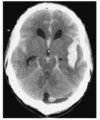

What is the diagnosis

Identify the arrowed features on the scan

SAH with evidence of hydrocephalus

- Blood in sulci

2 + 3: Frontal and occipital horns of the lateral ventricles are dilated as is the third ventricle (4)

There is intraventricular blood (5)

The low-denstry area around the frontal horn represents transependymal flow (6) due to acute hydrocephalus

Blood is seen in the right sylvian fissure, 7, and in the interpeduncular cistern, 8 and the right and left, 9 10, ambient cisterns.

The quadrigeminal cistern 11 is clear of blood.

The temporal horns of the lateral ventricles are dilated